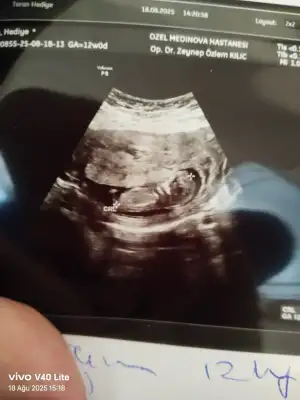

Merhaba arkadaşlar Sizce cinsiyet nedir 12 haftalık iken . İkili tarama için özele gittim doktor bir yorumda bulundu 15 haftalık kendi kendi doktoruma gittim o da bir yorumda bulundu ama ben sizin düşüncelerinizi merak ediyorum iki doktorun da kız yönünde tahmin yaptı ama kesin bir şey demediler ilk 2 fotoğraf 15 haftalık öbürü de 12

12 hafta da bile kemikleri oluşmuş sanki erkek bebek erken gelişir miş kız bebeye göre 12 hafta da da oluşmuş durumda bebisiniz onun için erkek gibi geldi bana